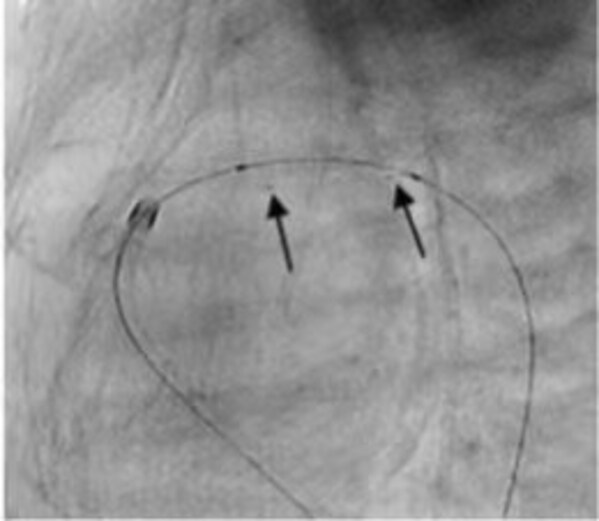

成功應(yīng)用IBS Angel(TM)對(duì)動(dòng)脈導(dǎo)管進(jìn)行開(kāi)通。術(shù)后即刻隨訪結(jié)果顯示支架形態(tài)結(jié)構(gòu)良好,患者動(dòng)脈導(dǎo)管內(nèi)血流通暢